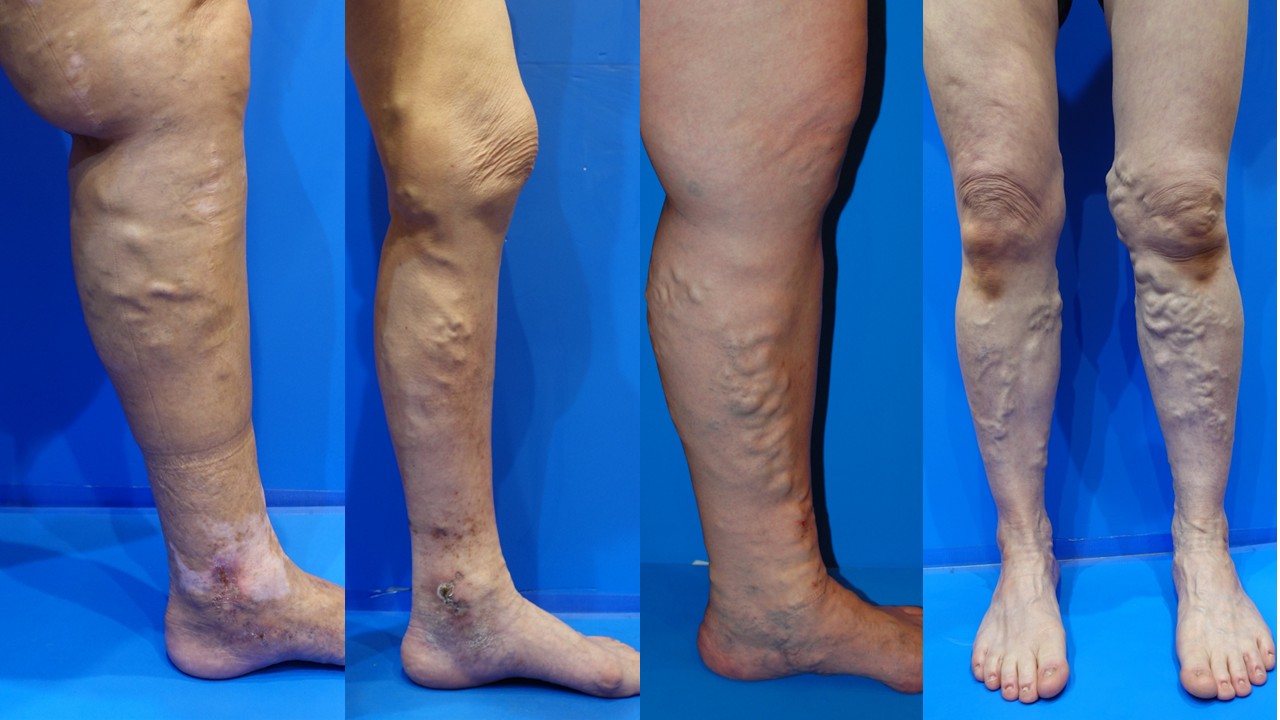

下肢静脈瘤で特に重要なサインは、

足の血管がボコボコ・クネクネと浮き出ているかどうかです。

足の血管 ボコボコ

まず確認してほしいのは「血管がボコボコ浮き出ているか」です

下肢静脈瘤は、足の静脈の中にある弁が壊れ、血液が逆流することで静脈がふくらむ病気です。

そのため、典型的な下肢静脈瘤では、ふくらはぎや太もも、ひざ裏などに

ミミズのような血管、ボコボコした血管、クネクネと浮き出た血管が見られます。

足の血管 ボコボコ

下肢静脈瘤を疑いやすい足の特徴

- ふくらはぎの血管がボコボコ浮き出ている

- ひざ裏や太ももにクネクネした血管がある

- ミミズのような太い血管が見える

- 血管のふくらみに加えて、足のだるさや重さがある

- 血管のふくらみに加えて、こむら返りがある

- すねや足首の皮膚が黒ずんできた

- 足首まわりに湿疹やかゆみがあり、治りにくい

下肢静脈瘤で問題になるのは、単に血管が見えることではなく、

血管が太くふくらみ、ボコボコ・クネクネと浮き出ている状態です。

特に、ふくらはぎ、ひざ裏、太ももの内側などに、

立ったときに浮き出る太い血管がある場合は、下肢静脈瘤の可能性があります。

- 足の血管がボコボコ浮き出ている

- ふくらはぎにミミズのような血管がある

- 足の血管のふくらみが以前より目立ってきた

- すねや足首の皮膚が黒ずんできた

- 足首まわりに湿疹やかゆみがあり、なかなか治らない

長年放置すると皮膚の色素沈着、湿疹、皮膚炎、潰瘍などにつながることがあります。

特に、足の血管がボコボコ浮き出ていて、皮膚の黒ずみや湿疹を伴う場合は、

早めに専門医へ相談した方がよい状態です。